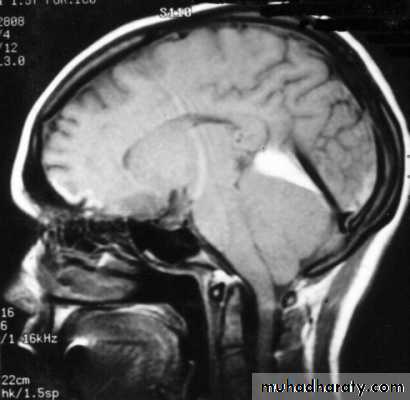

Increased Intracranial Pressure (Intracranial Hypertension)

The normal supine intracranial pressure is 5-15 mmHg (60-180 mmH2O).

An increase in the volume of any one of the contents of the skull will result in an increase in the intracranial pressure (ICP).

2. Obstruction to CSF pathways: as seen in:

a. Obstructive hydrocephalus.

b. Communicating hydrocephalus.

7. Cerebral Herniation

a. Subfalcine Herniation

b. Uncal Herniation

c. Tentorial Herniation

d. Tonsillar Herniation